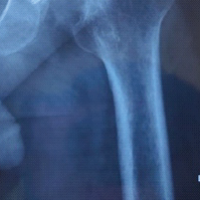

A 56-year-old male with chronic right knee instability and a history of posterior cruciate ligament and posterolateral corner insufficiency presented with varus alignment and decreased posterior tibial slope. He underwent a staged reconstruction beginning with a high tibial osteotomy (HTO) using patient-specific instrumentation, along with a tibial tubercle osteotomy (TTO) to correct deformity and offload posterior and lateral structures to improve both sagittal and coronal knee joint stability.

The osteotomy was performed using a patient-specific instrumentation guide (Bodycad, Quebec City, Canada) with a planned posterior tibial slope increase and valgus-producing biplanar correction. Fixation was achieved with a customized HTO plate and compression screws. The TTO was repositioned and fixed using large-fragment screws. The tourniquet was released following fixation, and initially, there was no concern for bleeding. However, during closure, brisk dark bleeding was noted. Pulses were no longer palpable or Dopplerable distally. Duplex ultrasound demonstrated no flow in the popliteal artery, raising concern for thrombosis or laceration. Vascular surgery was emergently consulted. Exploration revealed an intra-arterial thrombus and partial laceration of the anterior wall of the popliteal artery, distal to the osteotomy site (Fig. 3). A thrombectomy and primary repair were performed by the vascular team (Fig. 4).